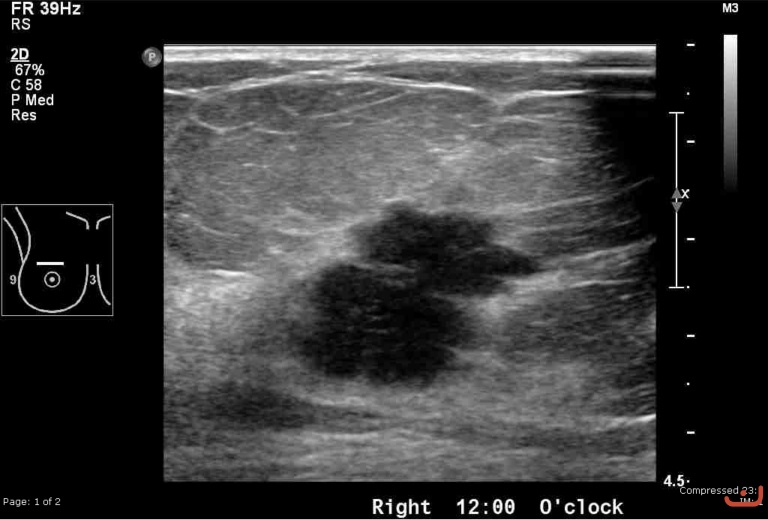

Malignant solid mass

Date

Thursday, 30 April 2015

File size of the original image

171.33 KB (768 x 520 px)